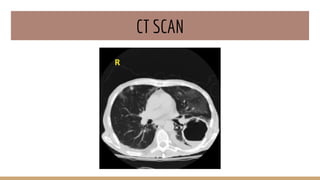

● CT Scan

CT SCAN